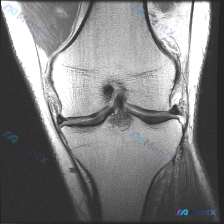

最近碰到一个有意思的病例:用户提示存在膝关节软骨异常,但提供的单张冠状位MRI却没有发现明确异常,整理一下分析思路和大家分享。 一、病例基础信息 这是一张单张膝关节MRI冠状位影像,分析可见: 1. 序列与解剖:为冠状位T2/质子密度加权序列,可显示股骨内外髁、胫骨平台、内外侧半月板及侧副韧带 2....